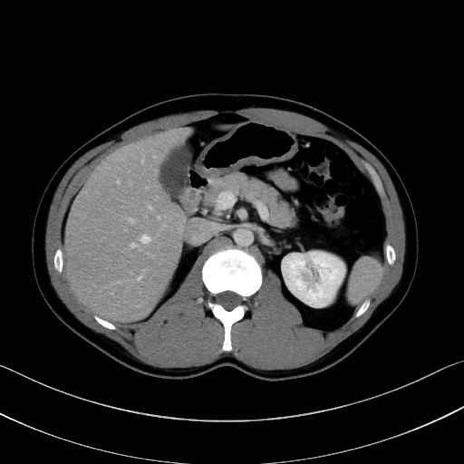

【症例】20歳代 男性 スクリーニング

■起始:典型的には腹腔動脈幹(celiac trunk)から左胃動脈・総肝動脈とともに三分岐し、脾動脈は左後上方へ向かう。

■走行:膵上縁または膵実質背側を蛇行しながら左方へ進み、膵尾部近傍で脾門へ至る。蛇行の程度は個体差が大きい。

■終枝:脾門部で複数の終末枝に分かれ、上極・下極枝や脾門枝群を形成する。胃短動脈群や左胃大網動脈はしばしば脾動脈から分岐する。